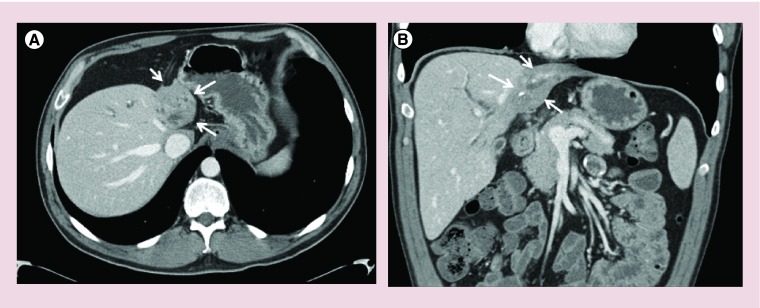

Figure 2. . Axial and coronal CT images demonstrating the ‘atrophy-hypertrophy complex’ in a patient with perihilar cholangiocarcinoma.

(A) Axial section demonstrating marked left lobe atrophy as highlighted by the arrows. (B) Coronal section demonstrating atrophy of the left lobe due to vascular involvement by tumor and compensatory hypertrophy of the unaffected right lobe.